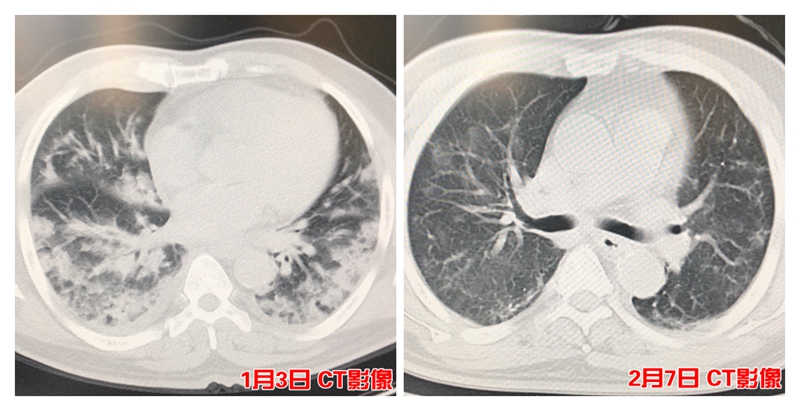

两侧白肺 多种致命并发症 从死神“抢”回性命

“患者当时已经是呼吸衰竭的状态,我们第一时间给上了呼吸机。”ICU主任郑孝敬说,CT检查显示患者两肺大面积感染,血氧饱和度仅为75%(正常值应在95%以上)。

ICU团队给予镇痛镇静、呼吸循环支持、抗病毒、抗炎、抗菌、化痰、拍背,同时俯卧位通气,气管切开、经常性的支气管镜吸痰等治疗,渡过呼吸衰竭及肺部继发细菌感染这一关。